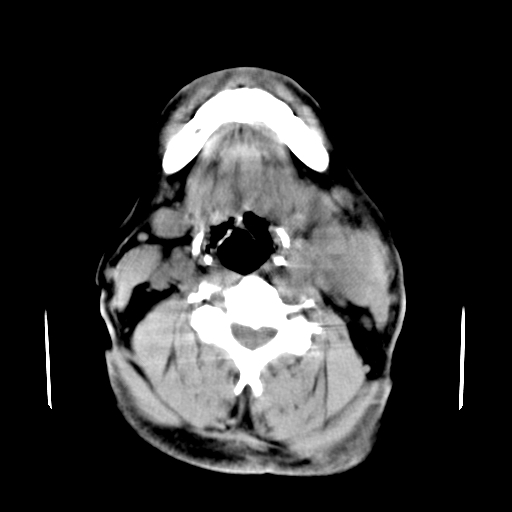

以下是引用卜一在2007-8-6 21:23:00的发言:[br]定位:左侧胸锁乳突肌内侧 颌下腺下后方。特征:弥漫性生长 软组织密度肿块,界限不清,内隐约见低密度坏死。考虑:神经源性肿瘤或血管源性肿瘤。

以下是引用wangzhanshuang在2007-8-6 21:08:00的发言:[br]腮腺混合瘤